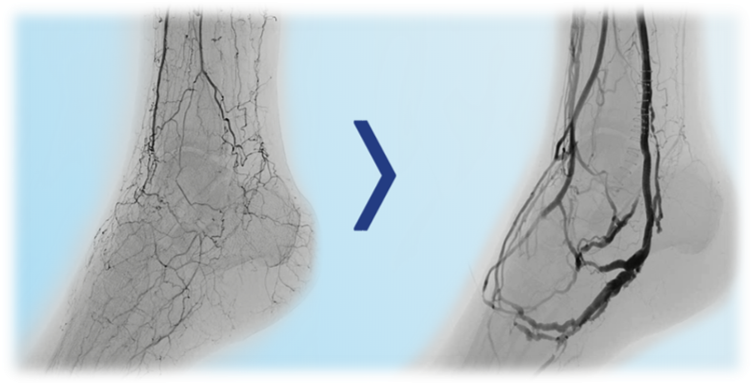

No SAD:足前部和跟骨动脉网络正常;

Moderate SAD:跖骨、趾骨、跟骨动脉弥漫病变;

Severe SAD:足弓、跖骨、趾骨、跟骨动脉闭塞或严重狭窄。

愈合率与保肢率:不同 MAC-score、SAD-score 组存在差异,如 12 个月保肢率约 80.5%-91.7%,24 个月伤口愈合率与流出道条件相关

长期数据显示 24 个月保肢率约 69%-85%;